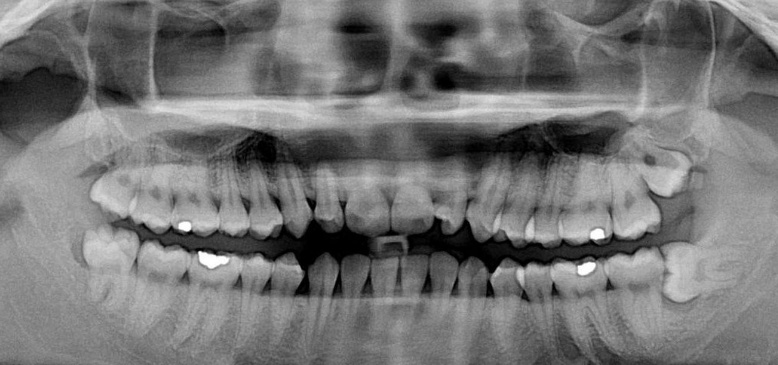

3、智齿缺失。在人类的进化的道路,我们的大脑挤满了头骨,下颚缩小,没有留给第三磨牙(智齿)的空间了。并且在几千年前人类开始烹饪食物并发展农业之后,饮食变得更加柔软,不需要再咀嚼坚硬的食物。智齿的存在显得有点多余。大约几千年前,一种涉及PAX9基因的突变出现,导致患者第三磨牙(智齿)发育不全,智齿缺失。根据一项研究表明,韩国人的患病率达到了41%,也就是说10个韩国人里面,有4个是没有智齿的。